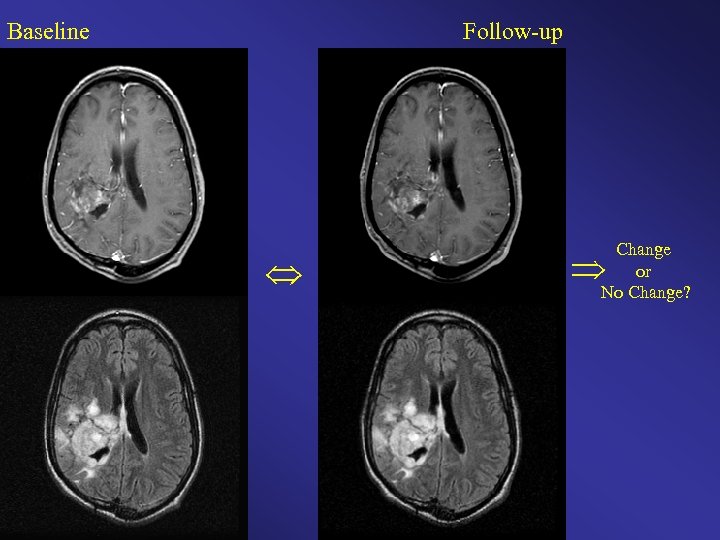

Baseline Follow-up Change or No Change?

Baseline Followup Change or No Change?